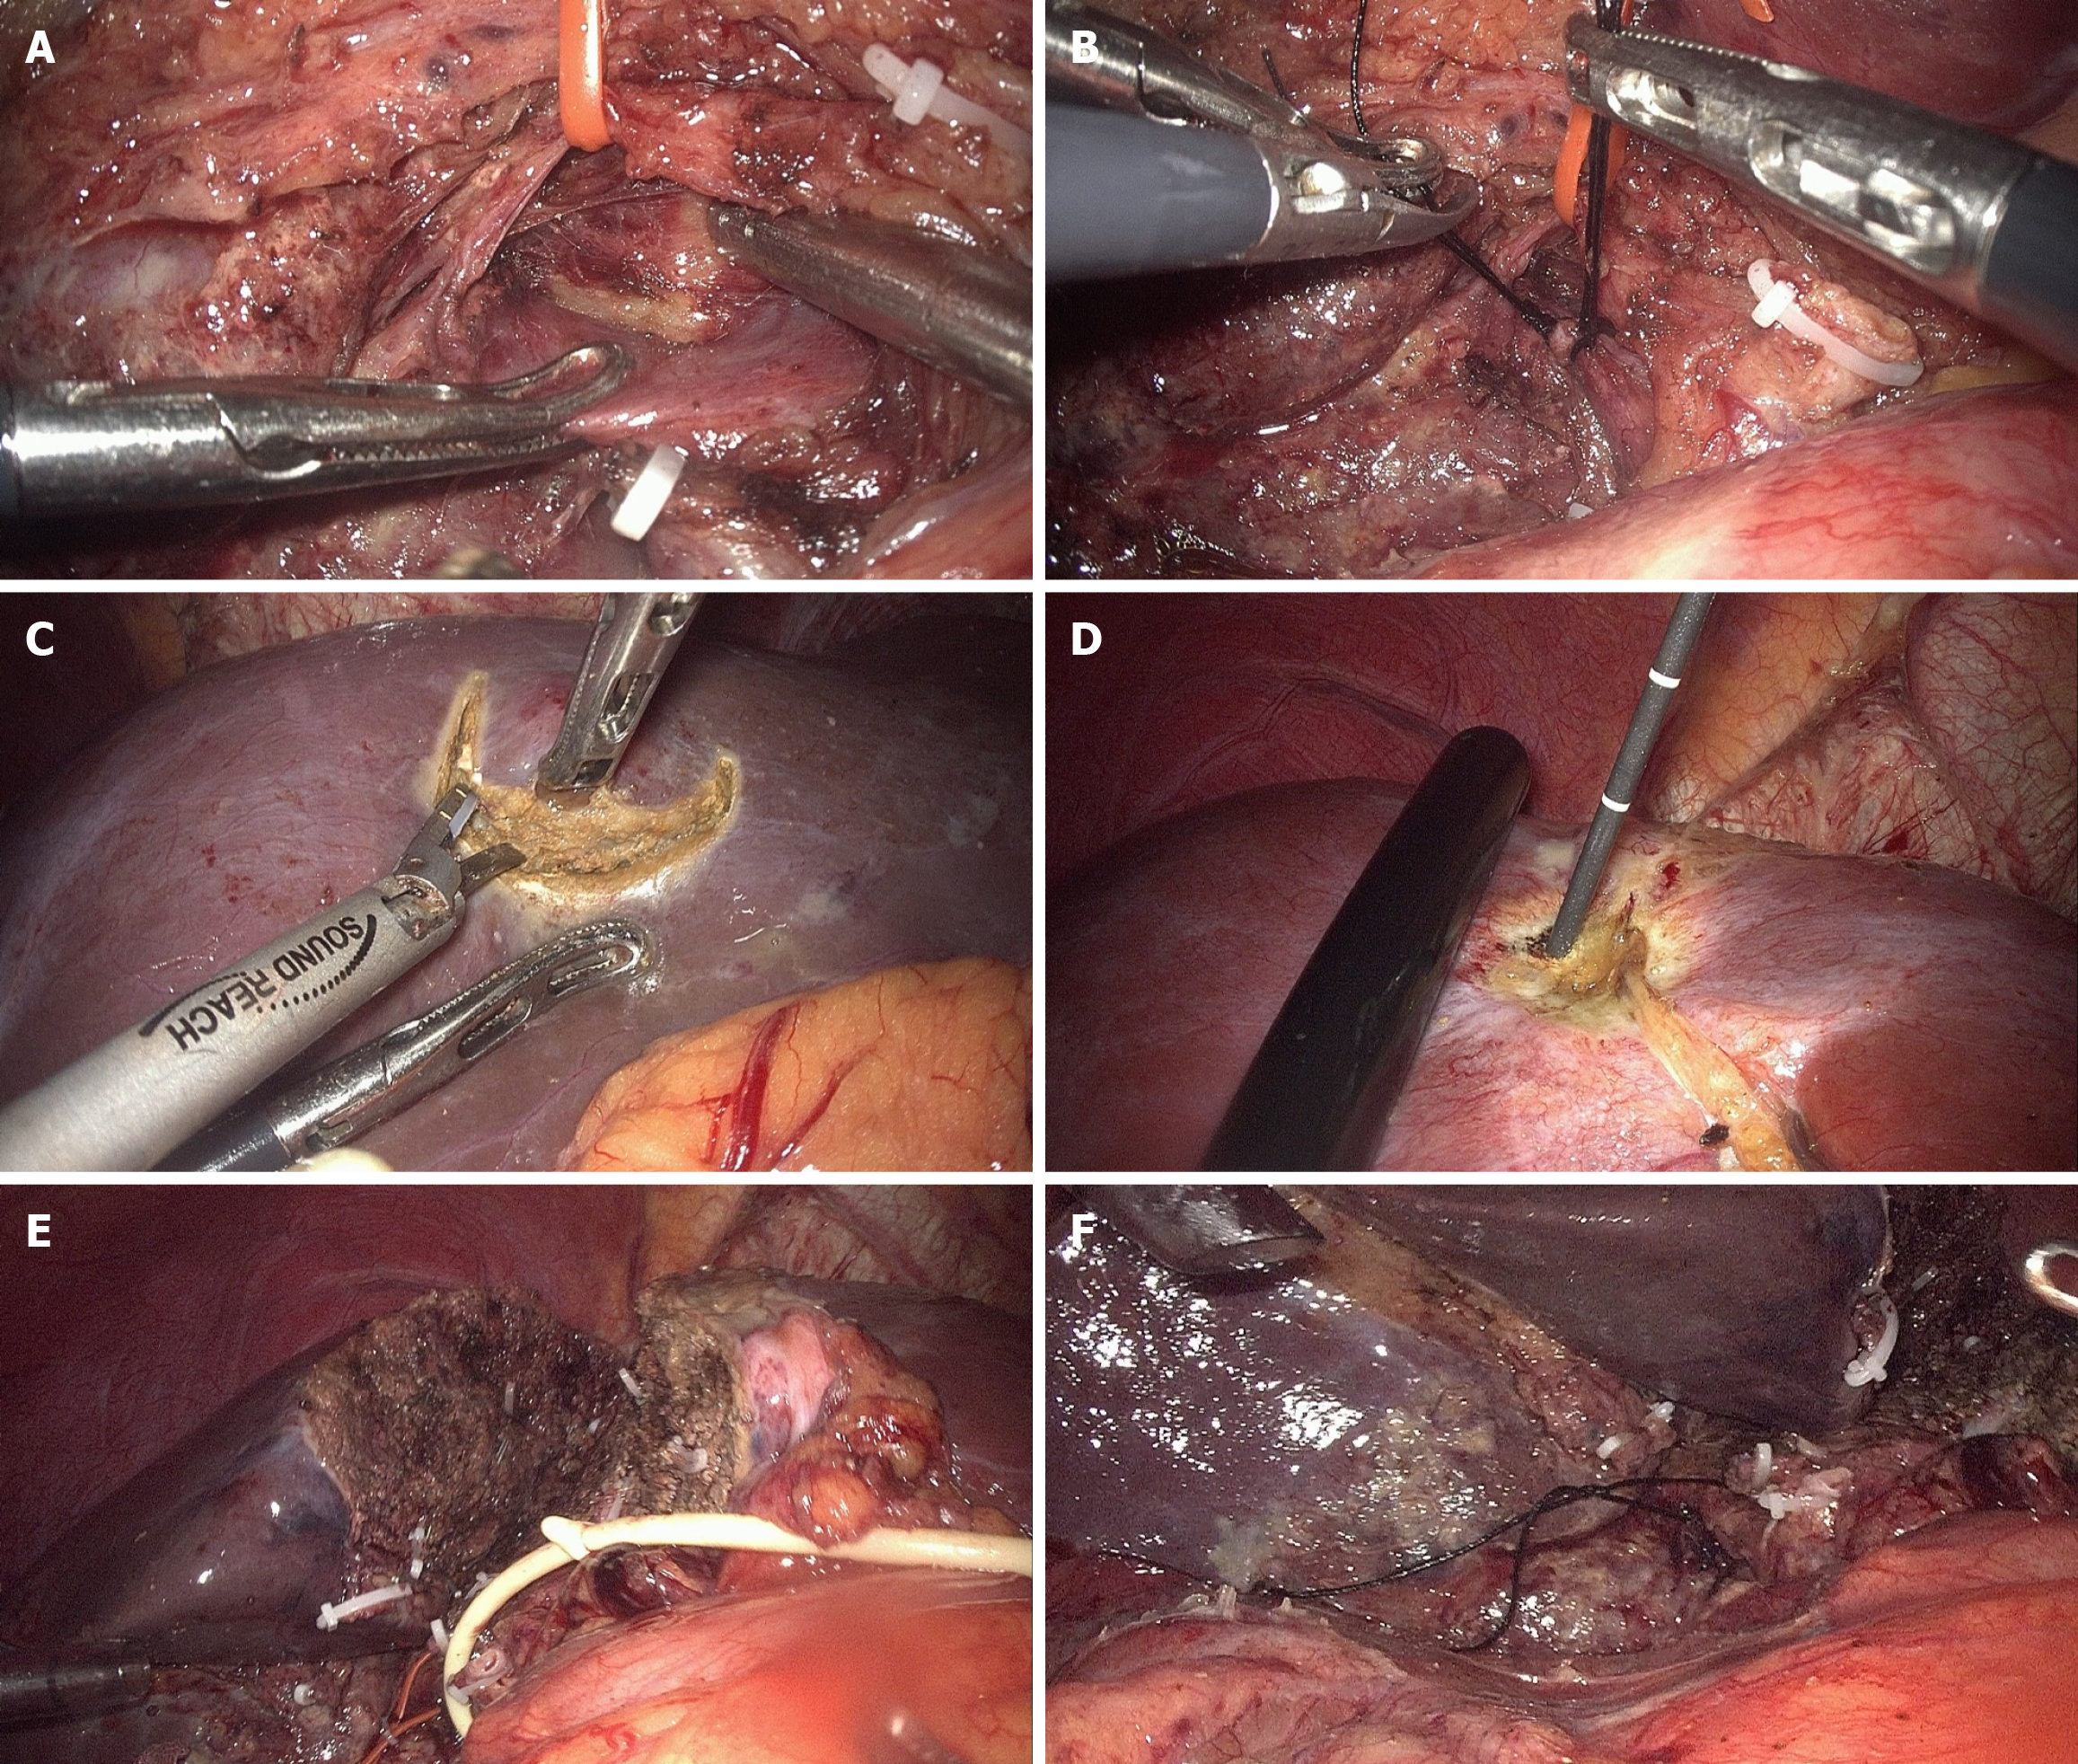

Figure 2 Main procedures in stage 1 of full laparoscopic associating liver partition and portal vein ligation for staged hepatectomy.

A: Identification of the right hepatic artery (RHA) and right portal vein with the RHA preserved using a tie; B: Ligation of right portal vein by double non-absorbable sutures; C: Radical resection of tumor in future liver remnant; D: Microwave ablation of tumor in future liver remnant; E: Partial transection of liver parenchyma in situ; F: Marking of the RHA is by a loose suture for identification during stage 2.